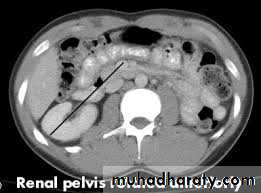

Pelvic kidney

This represents a form of renal ectopia. Prevalence is 1 in 2000–3000, withboth sexes affected equally.

The left kidney is affected more often than the right, and bilateral cases

are seen in <10%. The affected kidney is smaller, with the renal pelvis

positioned anteriorly (instead of medially), and the ureter is short but

enters the bladder normally.

Pelvic kidneys lie opposite the sacrum and below the aortic bifurcation

and are supplied by adjacent (aberrant) vessels (see Fig. 7.3). There is an

increased risk of congenital anomalies, including contralateral renal agenesis

and genital malformations.

Most cases are asymptomatic. Diagnosis is made on renal ultrasound

scan, IVP, or renography. Complications include obstruction, hydronephrosis,

and infection.